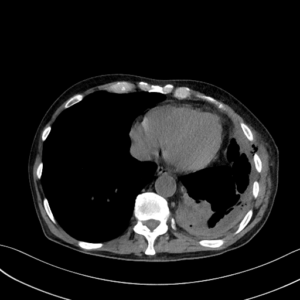

Ampiyem genelde ve en sık akciğerde enfeksiyona yani zatürreye bağlı gelişen bir komplikasyondur. Ağır bir akciğer enfeksiyonu sonrasında akciğer zarında sıvı toplanabilir (parapnömonik sıvı). Bu sıvıda enfeksiyon gelişir ise sıvı daha koyu kıvamlı, bulanık hatta daha yoğun, çoğu zaman kötü kokulu bir hal alacaktır. Bu duruma ampiyem diyoruz. Plevral sıvının enfekte olmasından bu sıvının bulanık beyaz-gri yoğun iltihap (irin) kıvamına gelmesine kadar farklı aşamalarda görülebilir. Bazı hastalıklarda, akciğer içindeki enfekte kavite, abse, enfekte kist vs. de plevraya açılabilir ve benzer ampiyem tablosuna neden olabilir.